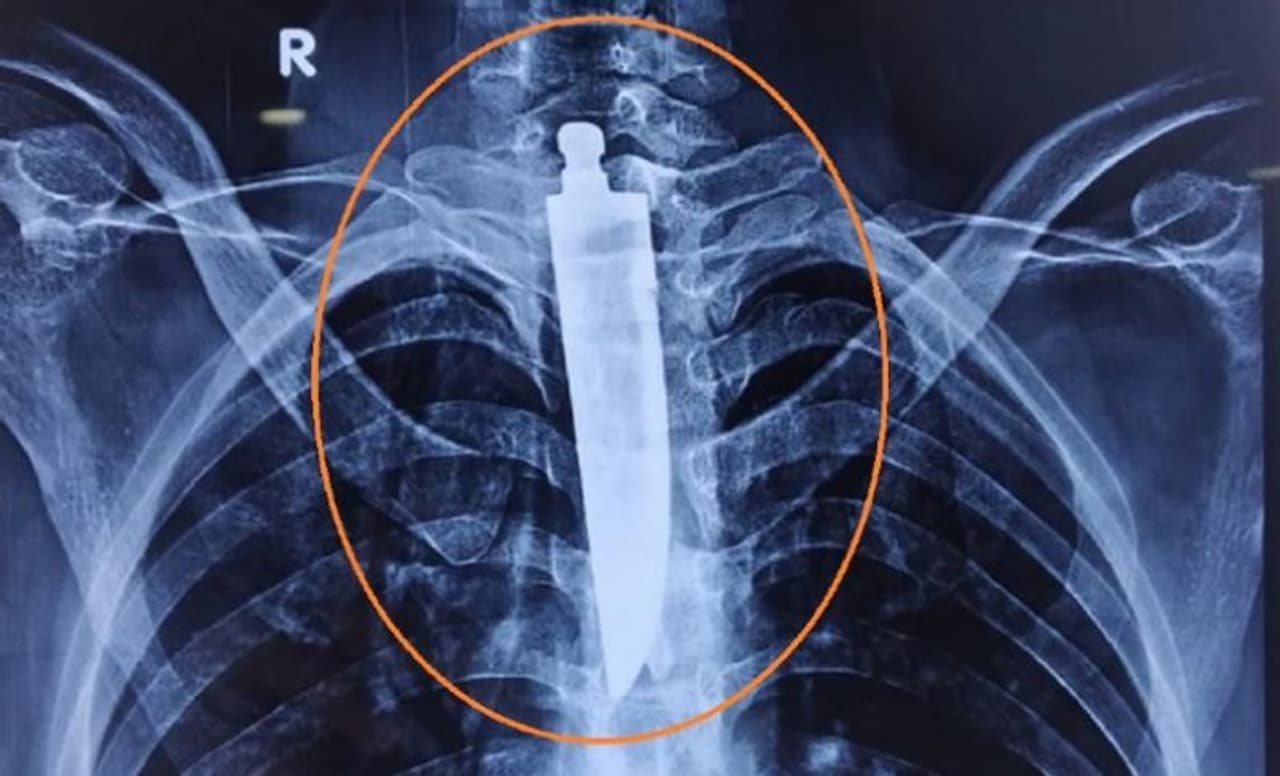

भोपाल (मध्य प्रदेश). कभी-कभी इंसान का आश्चर्यजनक चीजें मुंह में डालने का शौक बहुत भारी पड़ सकता है। इतना नहीं कई बार तो उसकी जान पर भी बन आती है। ऐसा ही एक हैरान करने वाला मामला भोपाल के अखिल भारतीय आयुर्विज्ञान संस्थान एम्स से सामने आया है। जहां एक 32 साल के युवक की सर्जरी कर उसके फेफड़े में फंसे 14 सेंटीमीटर (करीब 6 इंच) लंबे चाकू को किसी तरह निकाला गया है। आश्चर्य की बात यह है कि युवक ने चाकू से पेन की रिफिल भी निगल ली थी।

युवक के परिजनों ने बताया कि युवक को पिछले कुछ दिन से निगलने में परेशानी हो रही थी। इसके अलावा उसके गले में दर्द भी बना रहता था। जब उसकी ईएनटी विभाग के सर्जन डॉक्टरों ने उसकी गर्दन का एक्स-रे किया, तो वह यह देखकर हैरान रह गए। क्योंकि उसके फेंफड़ों में कुछ रॉड नुमा दिखाई दे रहा था। जब एंडोस्कोपी की गई तो पता चला कि चाकू फंसा हुआ है।

भोपाल एम्स के डॉक्टरों ने मामले को गंभीरता से लेते हुए युवक की फौरन सर्जरी करने का फैसला किया। भोपाल एम्स के निदेशक डॉ रमन सिंह ने मीडिया को बताया कि यह ऑपरेशन बहुत कठिन था, इसमें युवक की जान भी जा सकती थी। क्योंकि चाकू की लंबाई 14 सेंटीमीटर थी। जिससे एलिमेंटरी कैनाल के अलावा, यह मस्तिष्क को रक्त पहुंचाने वाली नसों को भी नुकसान पहुंचा सकता है।

एम्स के डॉक्टरों ने बताया कि चाकू ना अगला हिस्सा युवक के दिल की मुख्य धमनी तक पहुंच गया था। इसी बीच उसकी सर्जरी करना था। ऐसे में हमारी स्पेशल सर्जन टीम को इस ऑपरेशन करने में 4 से 5 घंटे का समय लगा। अब युवक पूर्ण रुप से ठीक है।